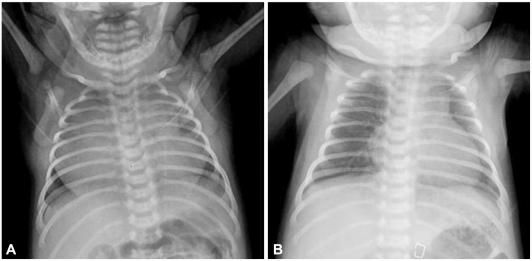

Right atrial aneurysm is an extremity rare congenital heart defect. We report a case which was diagnosed during the early fetal stage and operated on in a 2 week old neonate. Following median sternotomy, aneurysmectomy was performed under a cardiopulmonary bypass. Histopathological examination of the resected atiral tissue showed a lipotomatous degeneration and reduction of the muscular elements. There were no postoperative complications.